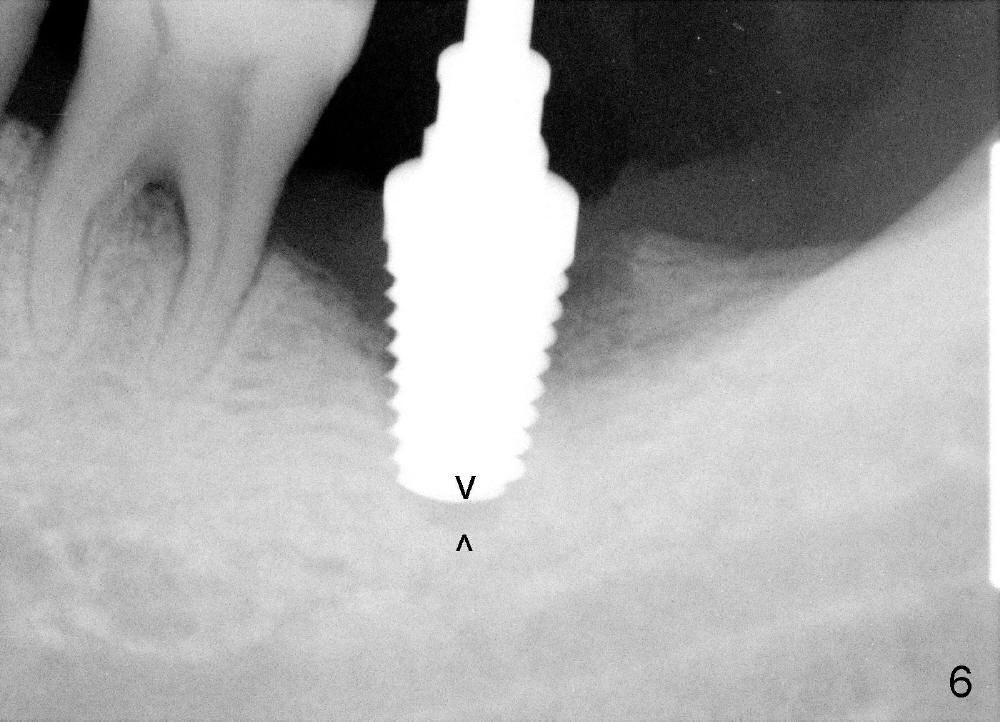

A 51-year-old man has generalized chronic periodontitis. The mesial root of #18 has vertical fracture (Fig.1*) with infection. The patient agrees extraction (Fig.2) and immediate implant. The septum is thin. The pilot drill drops into either the mesial (Fig.3) or distal sockets. Furthermore it is difficult to control pain probably due to severe infection (Fig.2 >: mesiobuccal erythema and edema). Repeated local infiltration does not alleviate pain associated with drilling. Block anesthesia has to be administered (one carpule of 2% Lidocaine with 1:100,000 Epinephrine). Damage to the inferior alveolar nerve (Fig.1 red dashed line) increases. On the other hand, osteotomy through the socket of the tooth with periodontits is easier because of shallow socket. Retraction of the buccal gingiva can reveal the bottom of the socket. We will increase the depth slowly until a tap obtains initial stability. The worst scenario is that active hemorrhage from the socket bottom is encountered initially. The nerve injury can be reduced minimally.

How about flatten the septum (Fig.4 white lines; from inset A (post extraction) to B)? When the septum is level with the mesial and distal sockets, a drill easily penetrates the middle of the socket (Fig.3 inset C). With strict control of depth, the osteotomy increases until a 6x14 mm tap gets initial binding to the socket (Fig.5: depth 11 mm). After increase in the depth by 1-2 mm, PA is taken with a 7x14 mm tap (Fig.6). There is a gap that the tap or the corresponding implant can engage further (between arrowheads). After increase in the diameter in the bottom of the osteotomy, a 7x11 mm implant is placed with insertion torque between 45 and 50 Ncm; the threads of the implant have tight contact with the bone (Fig.7). With the large diameter implant, the socket opening is closed without too much tension (Fig.8). The wound is protected with perio dressing. Postop there is no paresthesia. Pain is controlled by Hydrocodon/Acetaminophen. A long acting local anesthetic (Marcaine) should have been used immediately postop. Next morning, the patient is pain free. A short implant should be used in a critical area such as the lower 2nd molar where the inferior alveolar nerve is nearby. However, the implant is found unstable 1 month postop.